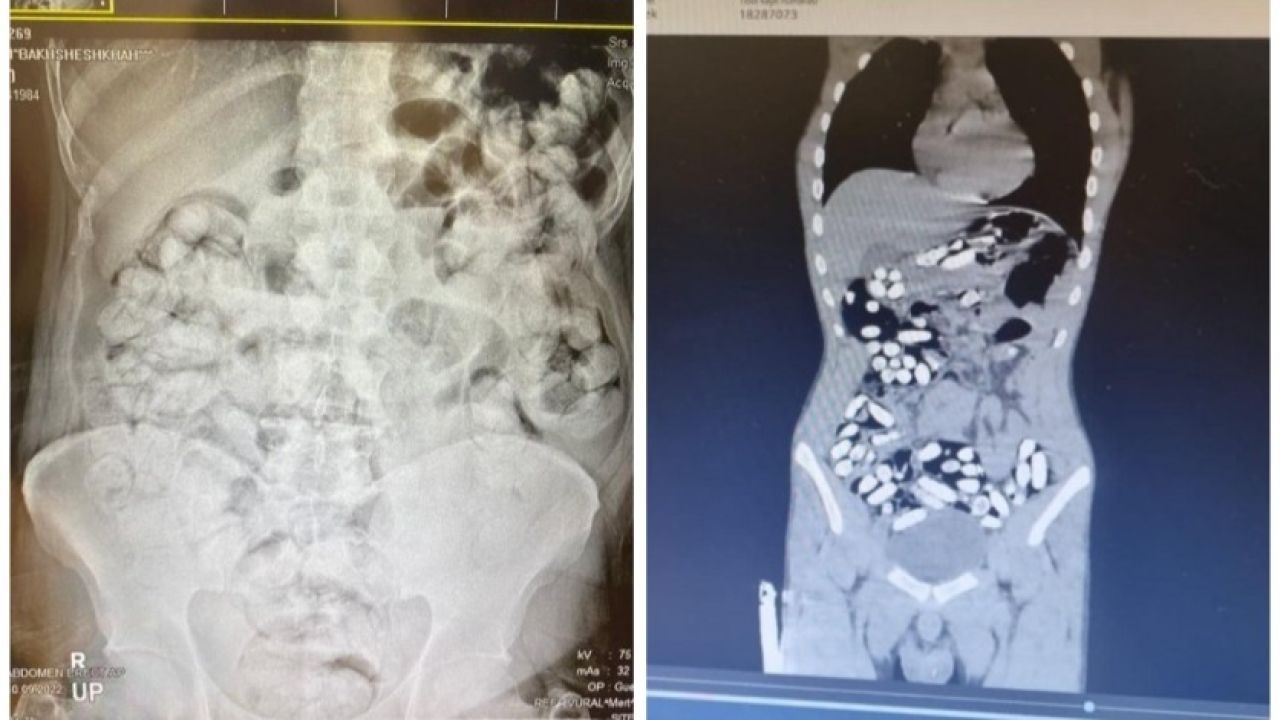

Çekilen röntgen filmlerinde şüphelilerin vücutlarında 62 kapsül eroin ve 210 kapsül afyon sakızı olduğu tespit edildi.

Röntgen çekimlerinde uyuşturucu kapsüllerinin şüphelilerin neredeyse iç organlarının her tarafına yayıldığı belirlendi. Doktor ve polis, vücutta tek seferde bu kadar yüklü miktarda uyuşturucu görmenin şaşkınlığını yaşadı. Gözetim altına alınan ve röntgenleri çekilen şüphelilerin vücudundan parça parça dışkılama yöntemi ile uyuşturucular çıkarıldı. Zanlıların hastanedeki işlemleri sürerken Narkotik Suçlarla Mücadele Şubesi ekiplerinin teknik ve fiziki takiplerinde, benzeri yöntemle yine aynı güzergahtan uyuşturucu götürüleceği bilgisi alındı. Bunun üzerine uygulama noktasında durdurulan bir otobüste, koltukta oturma şekilleri ile hal ve hareketlerinden şüphelenilen İran uyruklu Masoud T. ve Soleman O. gözaltına alınıp hastaneye götürüldü.